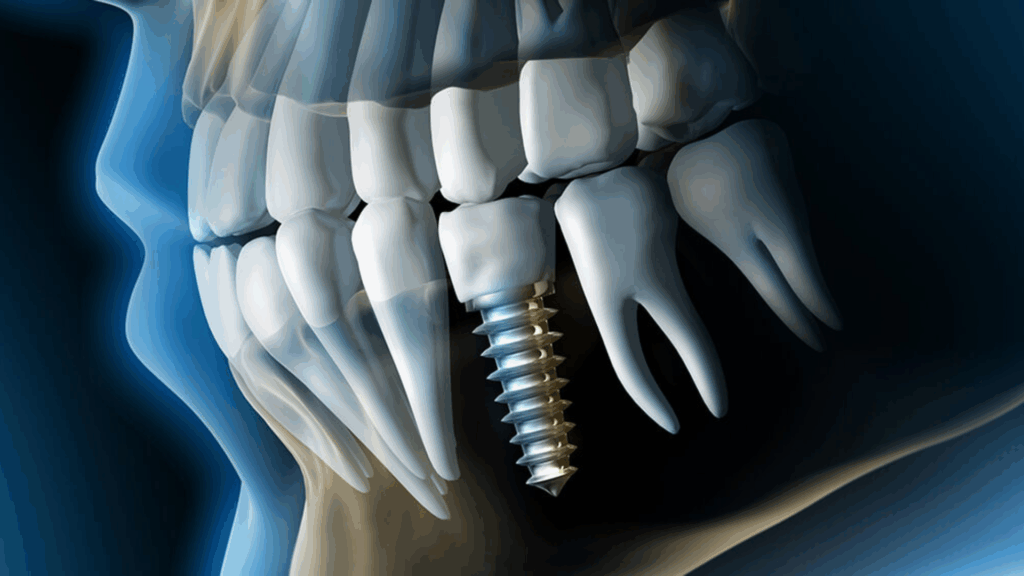

Why Lawrenceville Patients Ask About Digital Dental X-Rays Many Lawrenceville and Gwinnett County patients are more health-conscious than ever. When a dentist recommends X-rays, it’s natural to wonder about radiation exposure, safety, and whether digital dental X-rays are truly better than older methods. These concerns are especially common among parents, pregnant patients, and anyone who … Continued